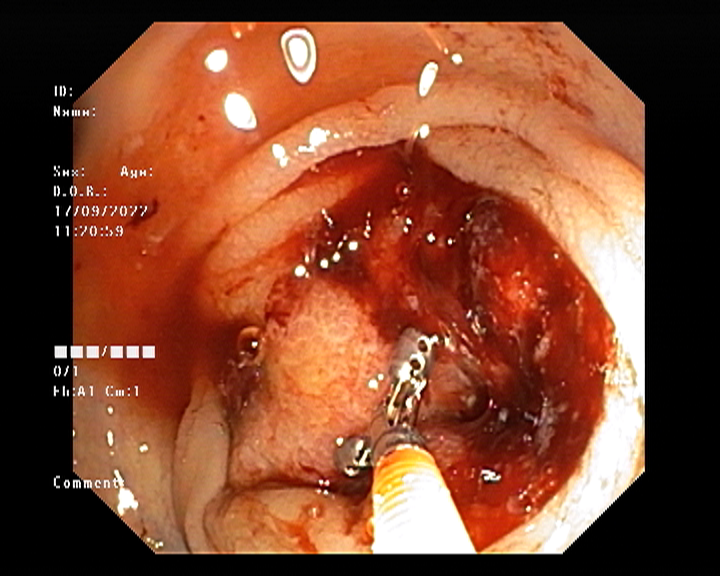

Endoscopy and colonoscopy are safe and accurate procedures used to directly examine the digestive tract and detect the root cause of chronic acidity, GERD, abdominal pain, bleeding, and bowel irregularities. These minimally invasive tests help identify ulcers, inflammation, infections, polyps, strictures, and early cancerous changes.

At Sapphire Gastroenterology Center, modern endoscopic equipment ensures precise diagnosis and, when required, therapeutic intervention during the same procedure. Based on findings, targeted treatment plans are created, including medication, diet guidance, and preventive strategies. Early diagnosis through endoscopy and colonoscopy plays a crucial role in preventing serious complications and improving long-term digestive health.